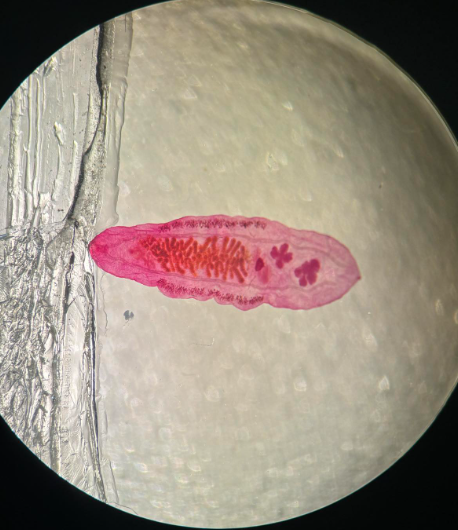

paragonimus wersermani postać dojrzała

opisthorchis felineus postać dojrzała

fasciolopsis buski postać dojrzała

clonorchis sinensis postać dojrzała